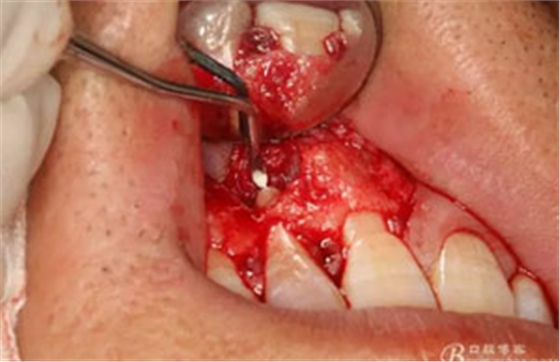

圖14.超聲骨刀切除根尖組織3mm。

圖15.超聲骨刀修整切除后的根面,使其12根斷面平整光滑。

圖16。專用倒預(yù)備刀頭預(yù)備根尖3mm。